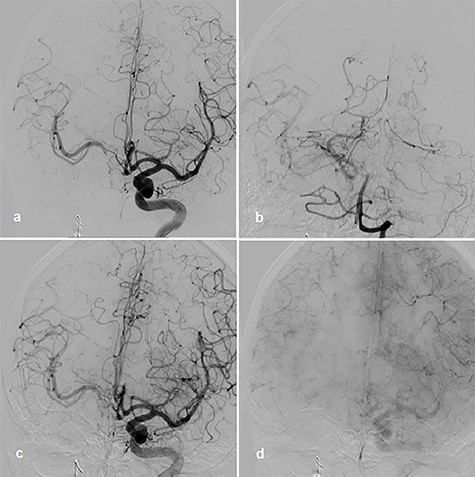

Therefore, the decision was made to use parent vessel occlusion. Initially, we performed a balloon occlusion test (BOT) with clinical evaluation as well as cerebral blood flow measurement by transcranial Doppler sonography (TCD). Initially, the systolic flow on the TCD in proximal medial cerebral artery (MCA) was 110–120 cm/s. Occlusion of the right ICA proximal to the stent with balloon a period of 30 min was performed. Left ICA and vertebral artery angiograms showed collateral perfusion of right hemisphere (Fig. 2a and b). There were no clinical symptoms over the time of BOT, but systolic flow reduction in the proximal MCA was observed up to 80 cm/s in the TCD.

BOT, left ICA angiogram with right-sided collateral perfusion (a); collateral perfusion via posterior communicating artery (b); left ICA angiogram during BOT and hypotensive challenge, arterial phase (c); venous phase (d).

Afterward, we decided to perform aneurysm coiling and PAO. Prior to this, we repeated the occlusion test with clinical, angiographic and TCD control before and during induced arterial hypotension. In stand-by anesthesia with central venous catheter and invasive blood pressure monitoring, a 4-F catheter was placed in the left ICA and a 6-F guiding catheter was placed in the right ICA. Occlusion of the right ICA was performed with a balloon. With 100 mmHg mean blood pressure, we measured 78 m/s systolic flow in the TCD on the right MCA. The patient presented no neurological symptoms. Left ICA angiogram showed good crossflow perfusion of the right side over the anterior communicating artery. After a drop of mean blood pressure from 100 to 70 mmHg using intravenous administration of urapidil, there was no neurological deficit observed over the period of 30 min. Furthermore, there was no perfusion reduction and no delay of venous phase on the right side on the angiogram of left ICA (Fig. 2c and d), but we observed systolic flow reduction from 78 to 50 cm/s on the right MCA in the TCD during induced arterial hypotension. Based on the results of good collateral flow during occlusion test without neurological deterioration after hypotension challenge, we finally performed PAO by coiling with seven coils (Fig. 3a).